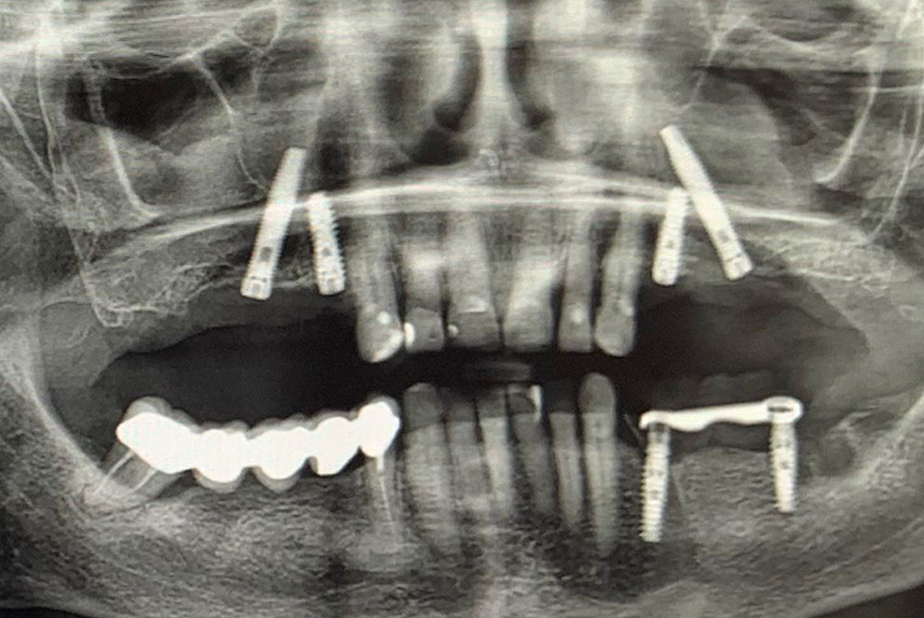

A seguito di un'accurata valutazione clinica e radiografica preparatoria (Fig. 1) è stato pianificato l'inserimento di impianti IS+ (BTK) nelle regioni anteriori e di impianti BT-Rhyno (BTK) nei settori posteriori mediante tecnica transinusale.

Fig. 1 - Valutazione clinica e radiografica preoperatoria